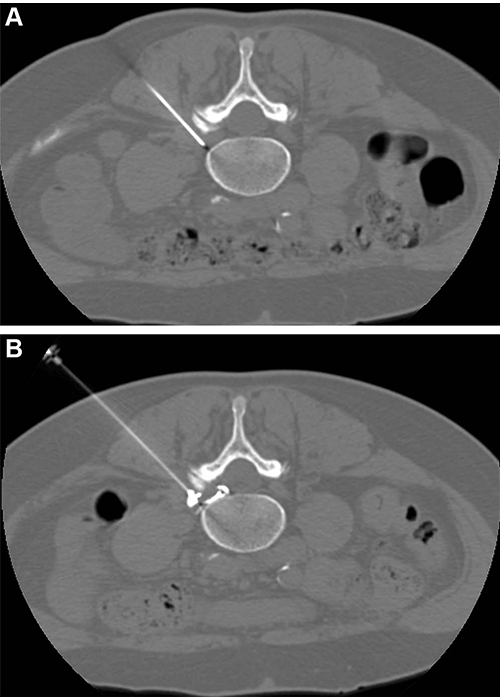

CT-guided pulsed radiofrequency (PRF) with transforaminal epidural steroid injection. A 62-year-old woman underwent PRF followed by transforaminal epidural steroid injection for sciatica due to left contained intraforaminal disk herniation at the L4-5 level. (A) A 22-gauge needle electrode with a 10-mm active tip was introduced and advanced using one 3-mm oblique axial unenhanced CT scan, which revealed that the needle tip was proximate to the target dorsal root ganglion with the lateral foraminal portal of entry. (B) Sensitive stimulation (50 Hz) PRF current with a threshold of no more than 0.2 V was used to confirm proper positioning by evoking tingling or electric pain in the dermatome that had to match the target dorsal root ganglion. Therapeutic PRF was then performed in one 10-minute session with E-dose functionality, maintaining temperature below the threshold for neural damage (42°C) and a constant voltage (45 V). Immediately after PRF administration, epidural spread of 0.3 mL of contrast material was confirmed using intermittent intraprocedural CT fluoroscopic imaging with no intravascular contrast material flow demonstration. A combination of steroid and anesthetic (1 mL lidocaine [ 20 mg/mL] and 2 mL dexamethasone [10 mg/mL]) was then injected without altering needle position to conclude the procedure.